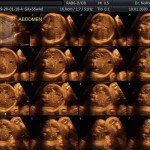

- Crecimiento fetal.

- La anatomía fetal: Diagnostico de Malformaciones Estructurales de aparición tardía (displasias esqueléticas, alteraciones cardíacas pequeñas, alteraciones de la vía urinaria y obstrucciones intestinales).